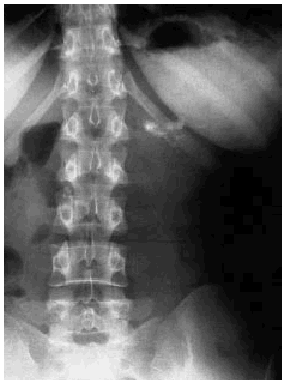

En las determinaciones analíticas practicadas destacaban: amilasas 350 U/l, y leucocitos, 14.000/ml, siendo el resto de la analítica habitual normal. Se realizó un test de sobrecarga oral de glucosa, que fue normal. Las cifras de magnesio sérico fueron 1,8 mg/dl (valores normales [vn], 1,8-2,9 mg/dl) y de selenio 76 ng/l (vn, 46-143). En la radiografía simple de abdomen se objetivaron calcificaciones en el hipocondrio izquierdo (figs. 1 y 2). En la ecografía abdominal se observaba una ectasia ductal pancreática y la presencia de calcificaciones grandes e irregulares localizadas en el cuerpo y en la cola del páncreas, siendo el resto de la exploración normal. Se realizó una tomografía axial computarizada (TAC) abdominal para completar el estudio, en la que se encontraron múltiples calcificaciones pancreáticas grandes localizadas de forma predominante en la cola pancreática, aunque alguna también en la cabeza, sin dilatación del conducto pancreático y con una disminución del volumen del parénquima pancreático respecto del que correspondería por su edad (fig. 3). También se realizó una gastroscopia sin alteraciones y un test de Van de Kamer, que fue normal.

Fig. 1.

A diferencia de la pancreatitis alcohólica, en que las calcificaciones suelen ser pequeñas, espiculadas, irregulares y mal delimitadas, la radiología de la pancreatitis crónica tropical suele evidenciar cálculos grandes (aunque variables en tamaño), bien delimitados y densos tanto en el conducto pancreático principal como en los conductos secundarios. Se suele observar también dilatación del sistema canalicular. La radiografía es de gran ayuda en el diagnóstico y, de hecho, en los países de alta incidencia constituye, junto a la clínica, el principal recurso diagnóstico20.